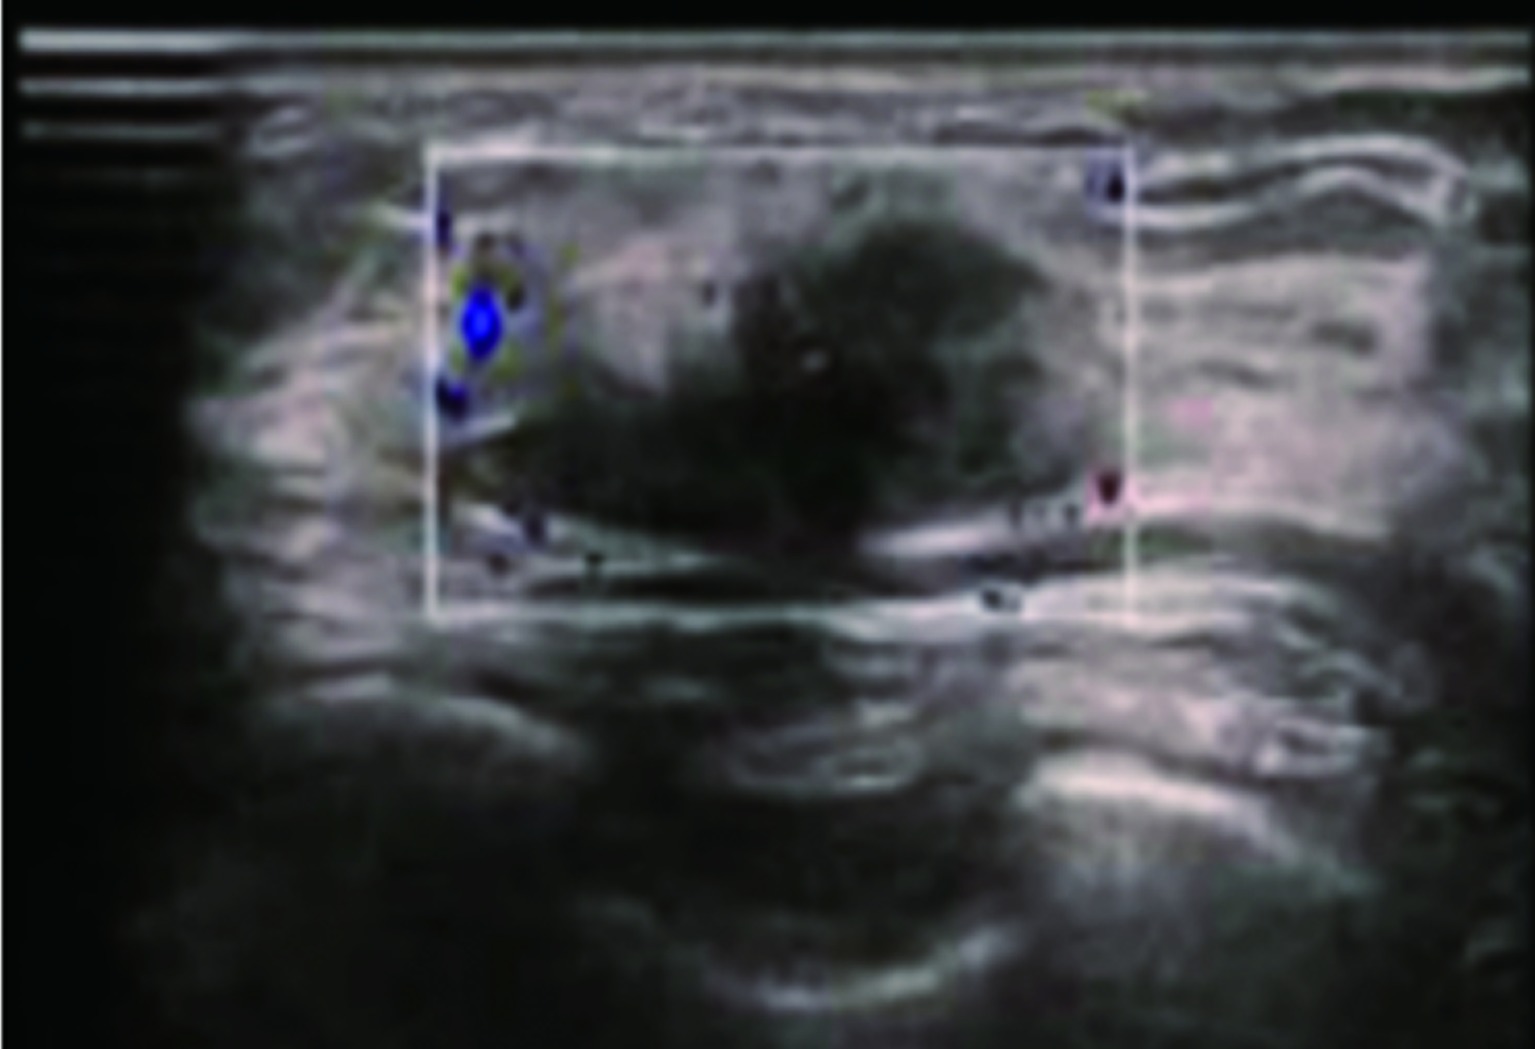

戈沙妥珠单抗于2022年6月正式被国家药品监督管理局批准上市,作为作用于Trop-2靶点的抗体偶联药物,为晚期三阴性乳腺癌患者带来了新的治疗选择。现报道1例晚期三阴性乳腺癌患者在病情出现进展时使用戈沙妥珠单抗治疗后情况,病情变化达到稳定,患者获益较为明显。